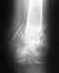

1. Закрытый перелом ключицы со смещением (поперечный, несколько косой). Лечение консервативное (8-повязка).

2. Сделано несколько снимков (фронтальных). Прошло 3 месяца, сращения крайне вялое, мозоли нет. И только косые снимки показали, что между обломками наблюдается некий зазор (м.б. за счет повязки, т.к. лямка давила только на плечо- только на эту часть ключицы).